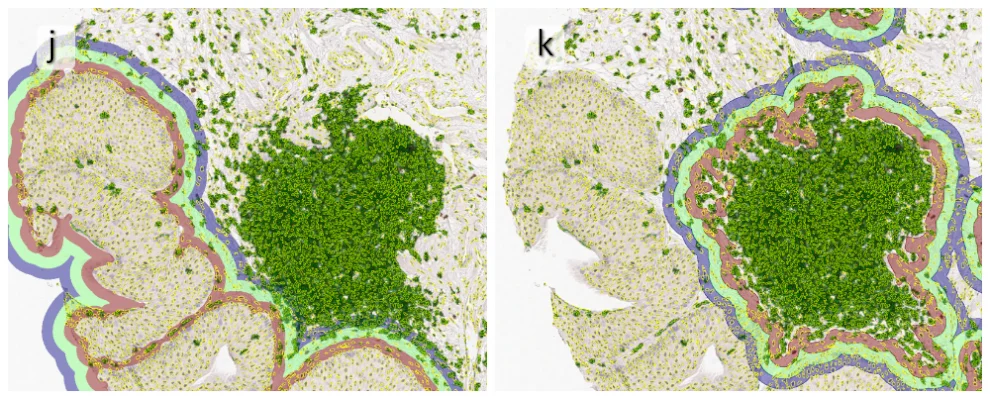

Beside the tissue classification itself, StrataQuest is capable of performing proximity analysis. It is possible to define specific proximity ranges; in the following case each range marked by different colors is 20µm. Nuclei detection was applied and CD3+ cells are shown in green, negative cells in yellow; (j) proximity ranges for the epithelium and (k) proximity ranges for the lymphocyte cluster.

Apart from visual image analysis, StrataQuest outputs quantitative numbers. This way, it is possible to acquire and validate much more information. For example, StrataQuest can show how many cells are detected in each range: through the establishment of gates, 5.06% of CD3+ cells were found to be very close (in 20 µm range) to the epithelium.